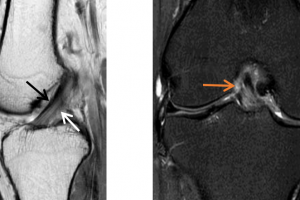

前交叉韧带(ACL),又称前十字韧带,是膝关节交叉韧带之一,位于膝关节内连接股骨与胫骨,主要是限制胫骨的过度前移,有固定骨骼和保持膝关节稳定的作用。ACL损伤是青壮年膝关节最常见的运动损伤,治疗不当可能会引起膝关节功能异常,导致膝关节功能性...

前十字韧带(ACL)是维持膝关节正常生物力学的重要结构,也是最容易出现损伤的韧带。在日常的打球、跑步甚至上下楼梯中都可能会出现前叉损伤。然而现实中很多人并不知道自己已经前叉受损了,依然继续运动,结果导致了更严重的后果! 怎么知道自己前叉是否...

前交叉韧带是连接大腿骨(股骨)和小腿骨(胫骨)的四根主要韧带之一,作用在于控制小腿向前伸,胫骨内旋,以及膝关节的稳定性,当运动时膝关节突然改变方向,急刹车,或者从高处跳下来,落在松软或者不平的地面上,韧带被过度拉伸,都可能造成前交叉韧带撕裂...